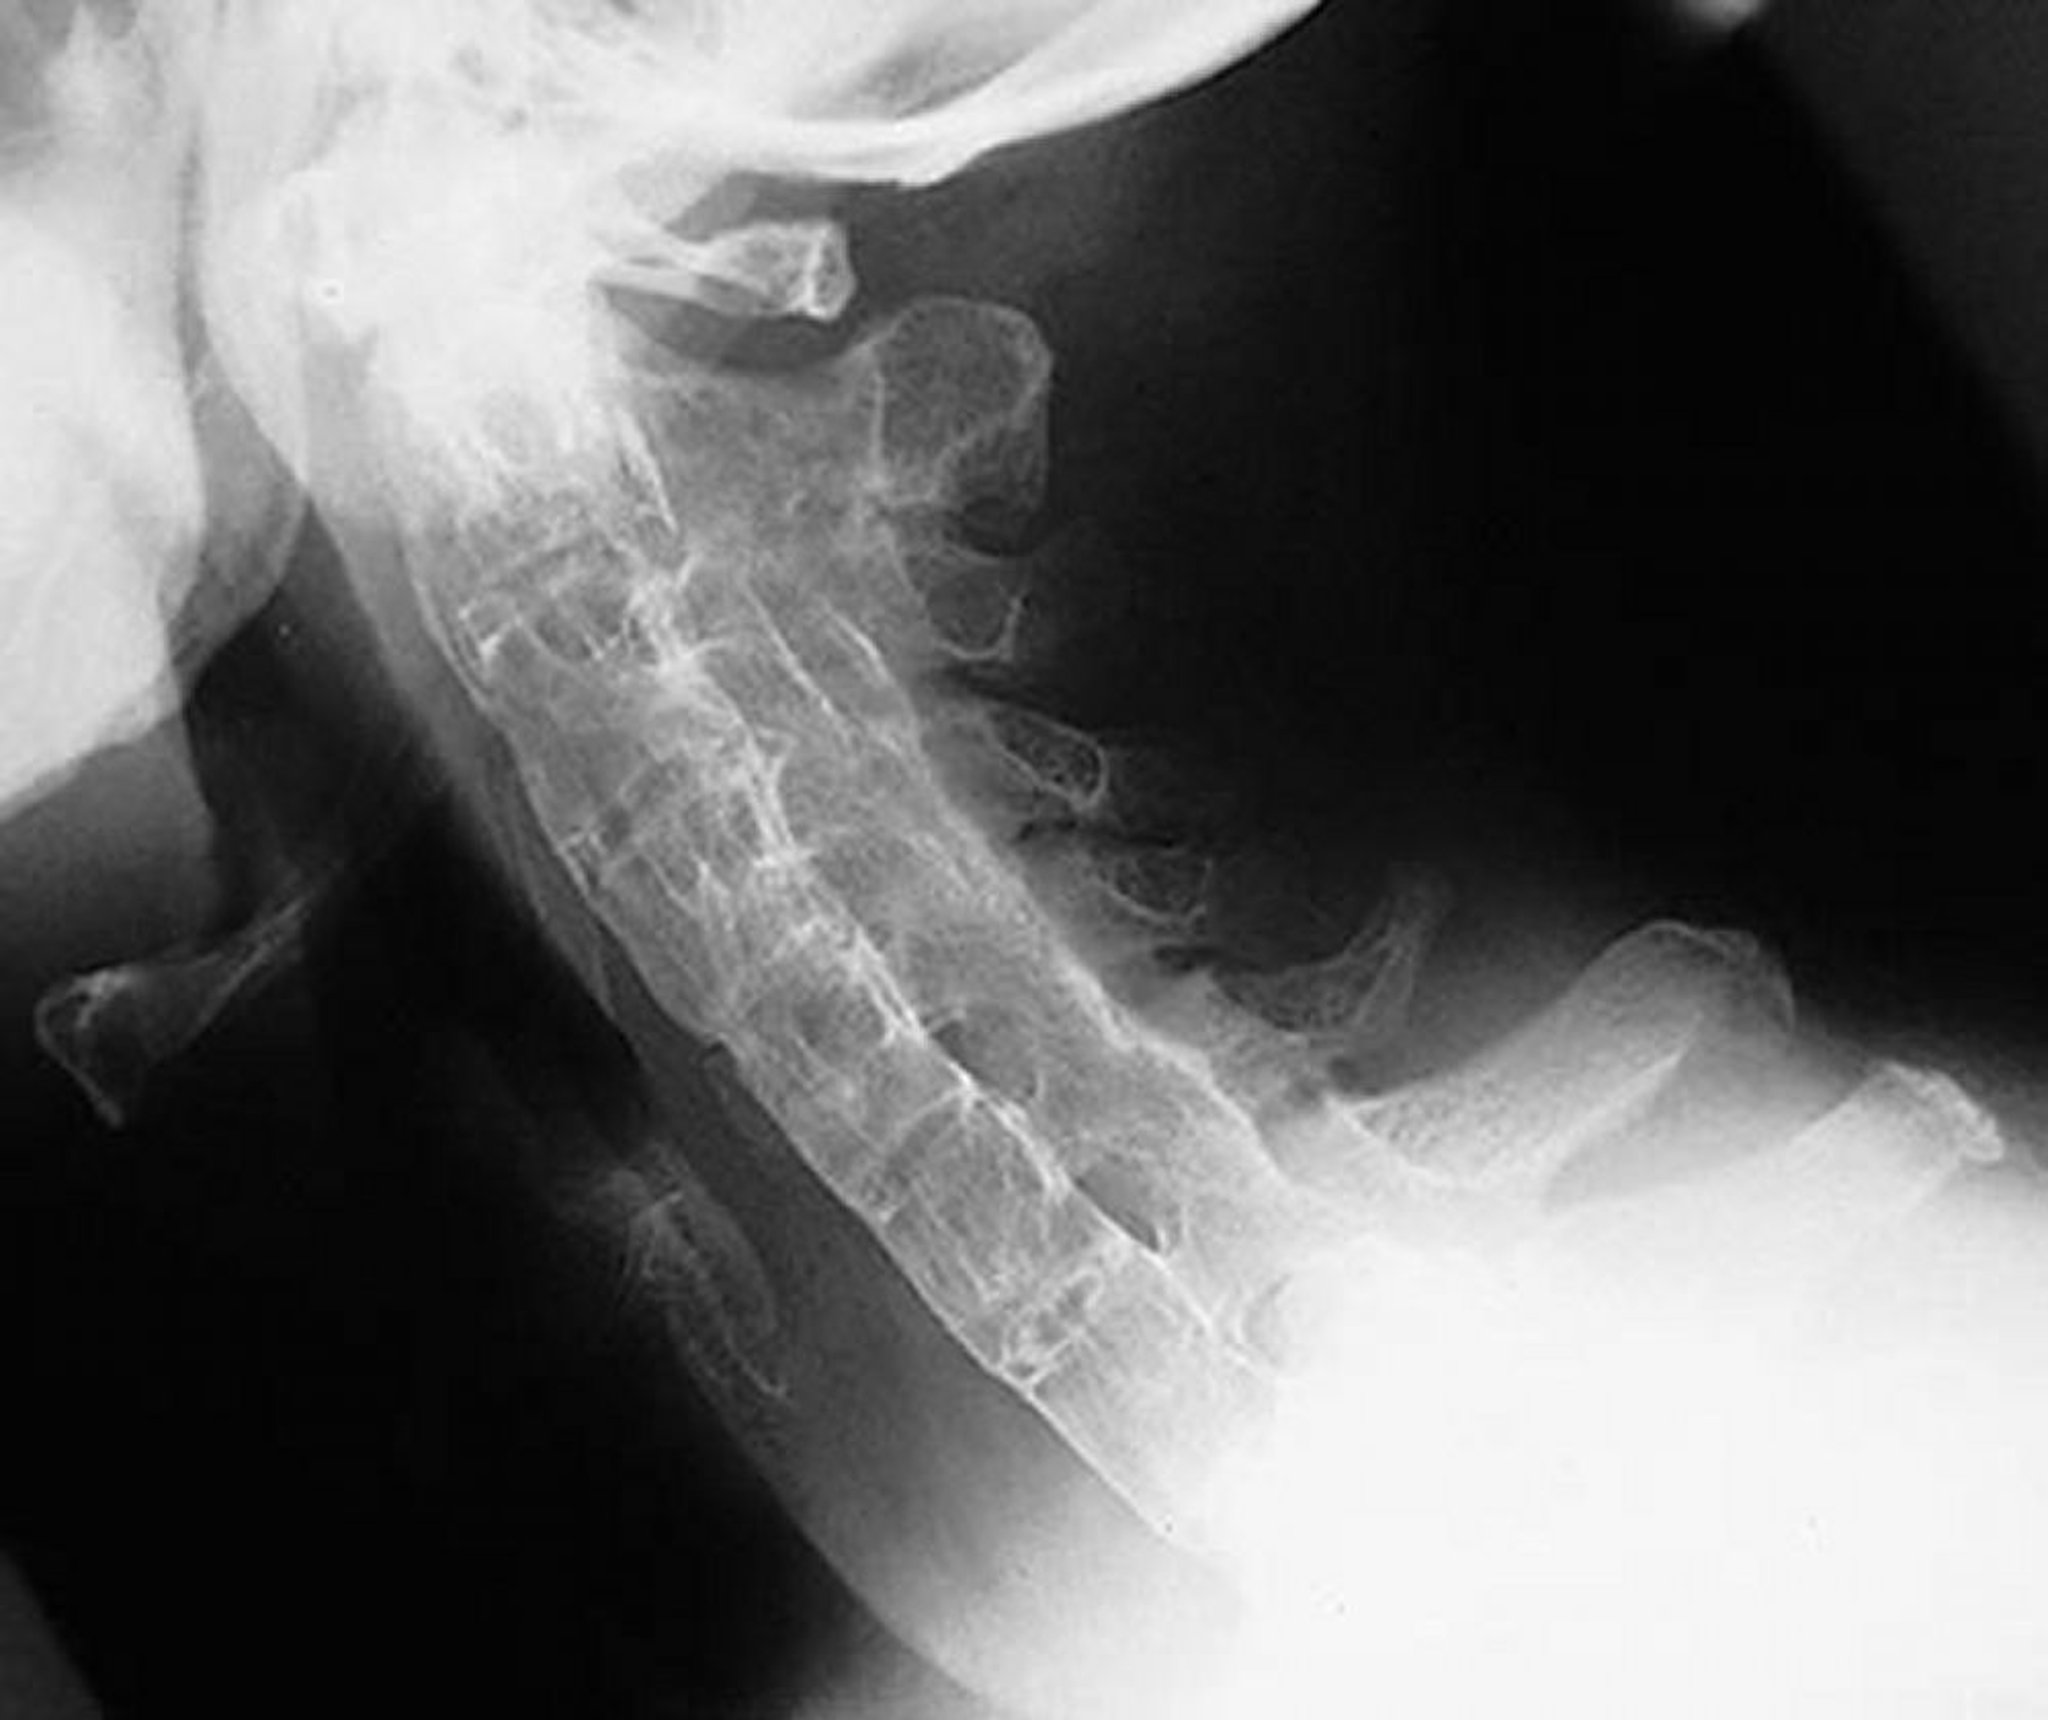

Colonne bambou dans la spondylarthrite ankylosante

Cette incidence latérale de la colonne cervicale montre une colonne cervicale rigide chez un patient atteint de spondylarthrite ankylosante sévère et ancienne. La colonne vertébrale est complètement ankylosée ("colonne bambou") par des syndesmophytes, des soudures des apophyses articulaires et des calcifications ligamentaires paraspinales.